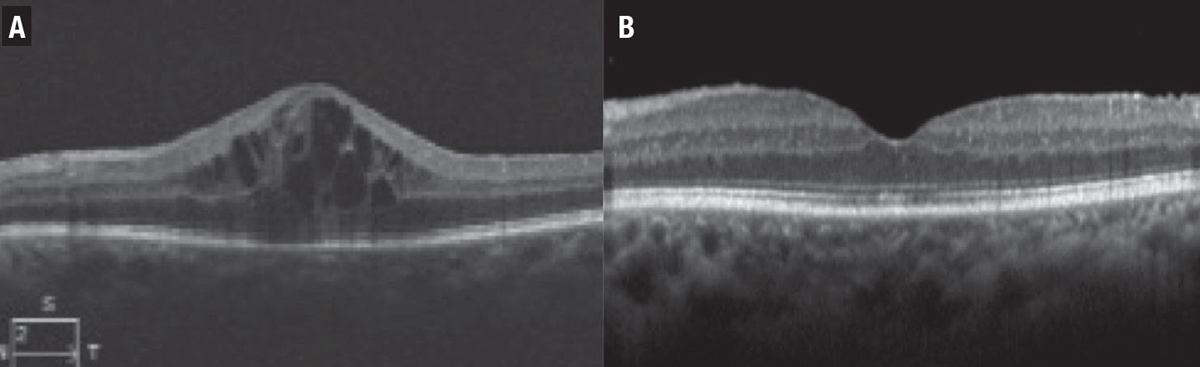

![]() |

| Figure 4. A 16-year-old girl had pars planitis and macular edema in both eyes. The edema (A) didn’t respond well to infliximab (Remicade, Janssen Biotech) and adalimumab (Humira, AbbVie). The patient was switched to tocilizumab (Actemra, Genentech) and the macular edema resolved after two months (B). |